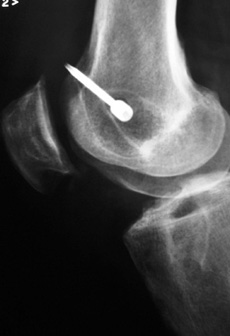

En todos los pacientes de ésta muestra fueron evaluadas radiografías y RMI para determinar las causas de la falla, dividiéndo a los pacientes en 2 grupos en virtud de si las cirugía primaria había sido efectuada por nuestro grupo de trabajo ó por otro. La causa más frecuente de fracaso en nuestra muestra fue el error técnico (75,8%), correspondiendo sólo el 46,8% a un túnel femoral anterior y el 28,5% a un túnel tibial posterior. (Figs.1, 2 y 3)

Figura 1: RX Cross pin protuyendo en artic. Patelofemoral. |

Figura 3: Cross pin protruyendo en articulación patelofemoral por túnel femoral anterior |